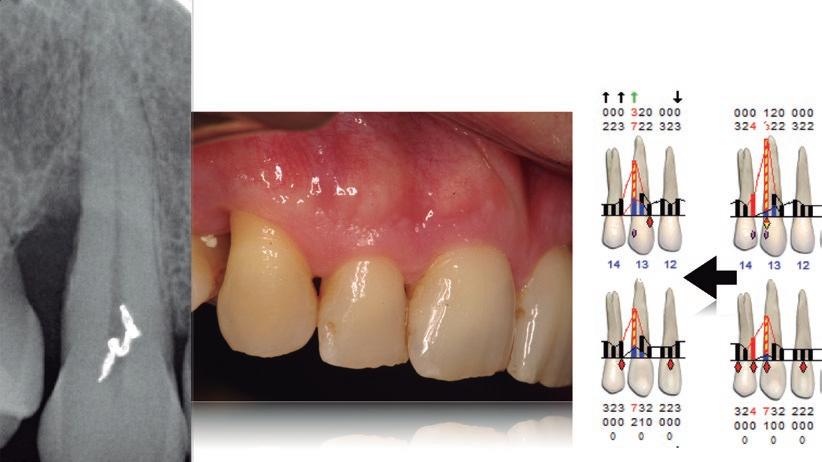

CASO 1

RDos meses de evolución del estado periodontal del diente 13 tras el raspado y alisado radicular.

SAcceso con microscopio donde se aprecia un defecto muy ancho y profundo. S Aplicación de proteínas derivadas de la matriz del esmalte.

SCierre primario sin tensiones. S Día de la retirada de sutura tras dos semanas de cicatrización.

REvolución radiográfica tras solo nueve meses utilizando únicamente proteínas derivadas de la matriz del esmalte junto a una técnica quirúrgica mínimamente invasiva.

según la clasificación de Lindhe28, esta movilidad probablemente tenga muy poco efecto sobre la regeneración. Pero si esta es grado II o III, independientemente de que pueda o no tener un efecto sobre la regeneración, resulta tremendamente complicado hacer este tipo de intervenciones sin ferulizar previamente el diente. En caso de que partamos de una moviliR Sondaje periodontal y aspecto clínico tras nueve meses de evolución.